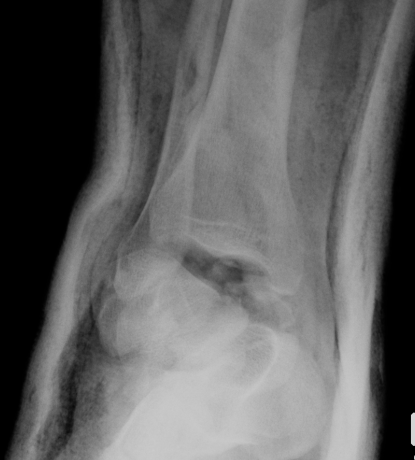

Xray / CT

Ensure no displacement / malalignment

Canale view

- evaluates talar neck

- foot everted 15 deg

- look for medial shortening / varus

Xrays

| AP | Lateral | Canale View |

|---|---|---|

| Entry point of the screws |

Evaluate neck reduction

|

Evaluates the neck reduction |

Lateral off articular surface Medial through articular cartilage |

Depth of screws |

Beam angled 75o to foot Foot 15o pronated |